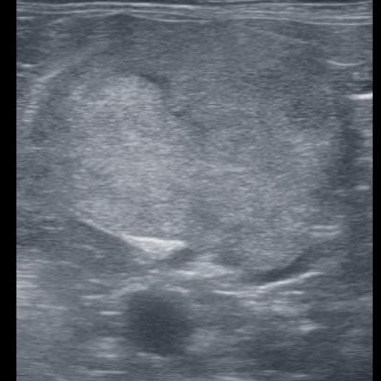

Dato che questi risultati hanno escluso alcune malattie (insufficienza renale e diabete, per esempio) ma non ci hanno indicato una patologia specifica, è stata effettuata una ecografia dell’addome. Da questa è risultato che è presente una massa abbastanza grande vicino al rene sinistro (foto in basso), compatibile, per la sua posizione, con la ghiandola surrenale sinistra. La ghiandola surrenale destra non era invece visibile. Questo quadro ecografico ci porta a sospettare la presenza di un tumore della ghiandola surrenale sinistra secernente cortisolo, che ha portato Maya ad avere la sindrome di Cushing.